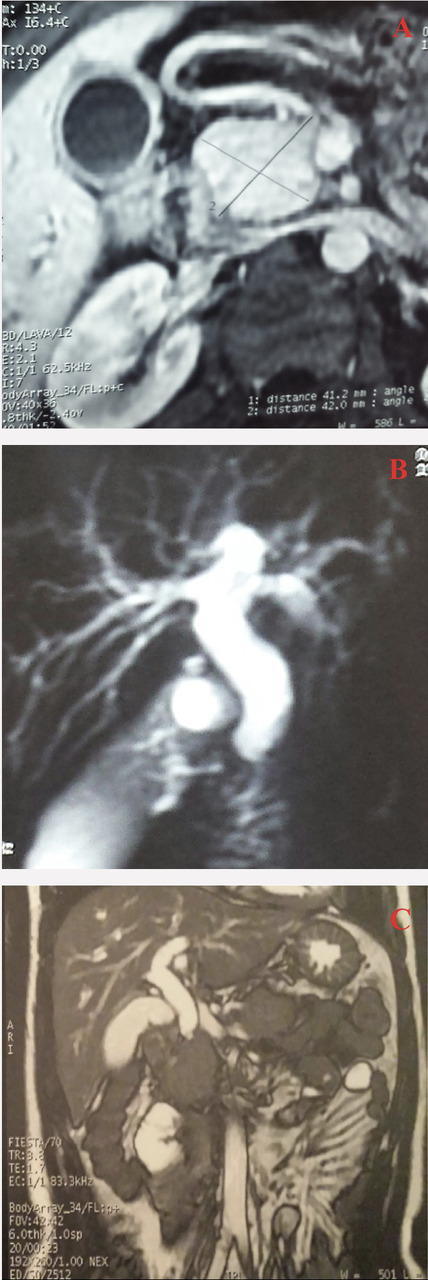

Cet homme de 29 ans avait depuis 10 jours un ictère apyrétique avec conservation de l’état général. La biologie montrait une cholestase avec cytolyse et une hyperbilirubinémie conjuguée à 196 mg/L. La cholangiopancréatographie par résonance magnétique (CP-IRM) montrait une hypertrophie diffuse du pancréas avec aspect de masse céphalique et dilatation des voies biliaires intrahépa-tiques et de la voie biliaire principale (14 mm) [v. figure]. Le taux d’immunoglobulines de type G était normal. Le diagnostic de pancréatite auto-immune pseudotumorale, sans distinction du type, était retenu, avec une rémission complète après 3 semaines de corticothérapie et un aspect normal du pancréas à la fin du traitement, sans dilatation des voies biliaires, et après un suivi de 22 mois. La coloscopie était normale.

La pancréatite auto-immune est une maladie rare qui peut s’apparenter à un adénocarcinome pancréatique. Classée en 2 types : le type 1 sclérosant lymphoplasmocytaire et le type 2 ductocentrique. Un troisième groupe est dit indéterminé quand les critères ne sont pas tous réunis et la distinction entre les deux formes impossible. La forme pseudotumorale est la principale manifestation clinique.1-2 L’imagerie est primordiale pour le diagnostic de pancréatite auto-immune, en particulier la CP-IRM distinguant une atteinte diffuse ou une forme pseudotumorale. Le traitement consensuel est la corticothérapie,3 avec une évolution spectaculaire faisant partie intégrante des critères diagnostiques, sans protocole standardisé. Le taux de récidive est de 30 à 40 %.